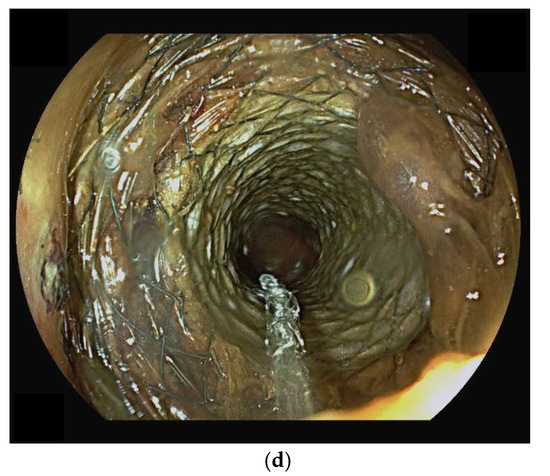

10. Endoscopic Ultrasound-Guided Entero-Colostomy with LAMS

- Neri, B.; Stigliano, S.; Biasutto, D.; Citterio, N.; Lisotti, A.; Fusaroli, P.; Mangiavillano, B.; Donatelli, G.; Tonini, G.; Di Matteo, F.M. Endoscopic ultrasound-guided entero-colostomy with lumen-apposing metal stent as a rescue treatment for malignant intestinal occlusion: A multicenter study. Endoscopy 2025, 57, 77–82. [Google Scholar] [CrossRef]